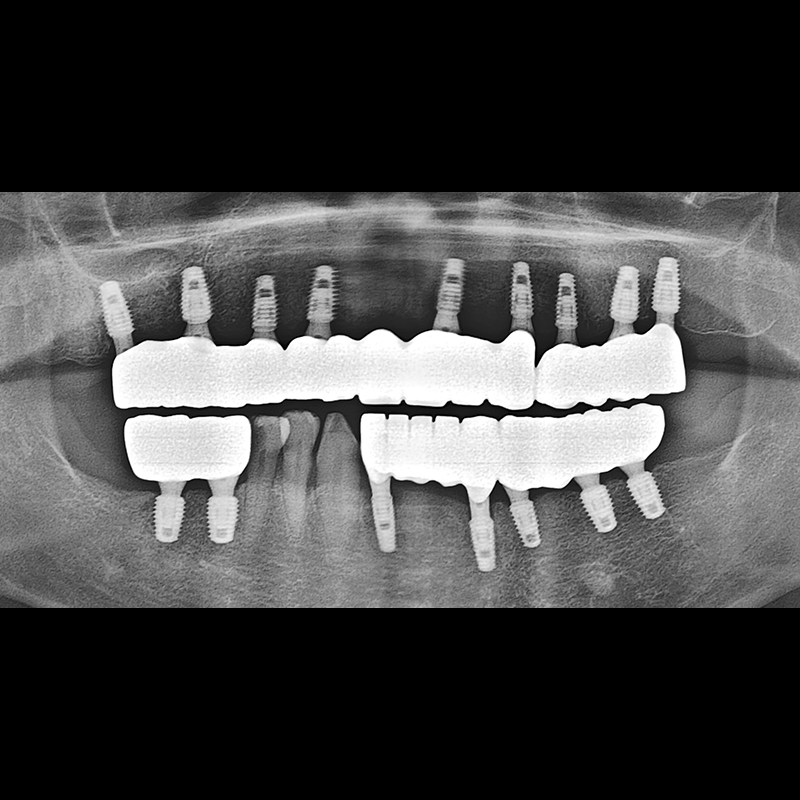

种植牙前后的照片 2025.05.30

在缺失的牙齿部分和难以挽救的牙齿位置植入了种植牙。